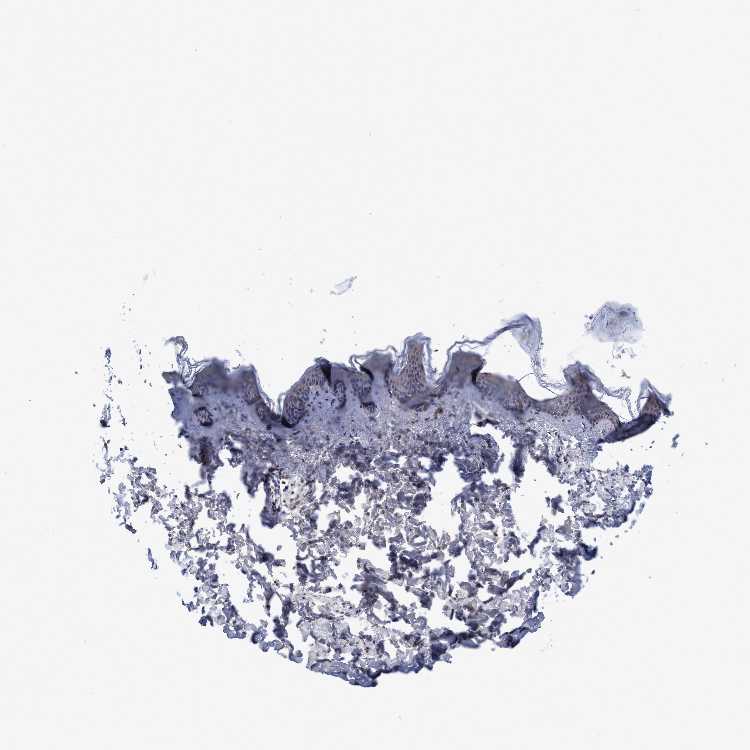

SKIN 1 - Antibody stainingi

Antibody staining in the annotated cell types in the current human tissue is reported as not detected, low, medium, or high, based on conventional immunohistochemistry profiling in selected tissues. This score is based on the combination of the staining intensity and fraction of stained cells.

Each image is clickable and will lead to virtual microscopy that enables deeper exploration of all samples and also displays staining intensity scores, fraction scores and subcellular localization as well as patient and tissue information for each sample.

SKIN 2 - Antibody stainingi